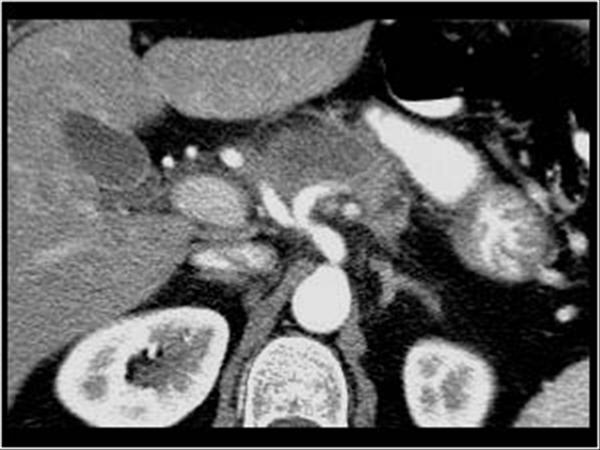

U tụy

» Thông tin: Nữ giới – 57 tuổi.

» Lâm sàng: Sút cân.